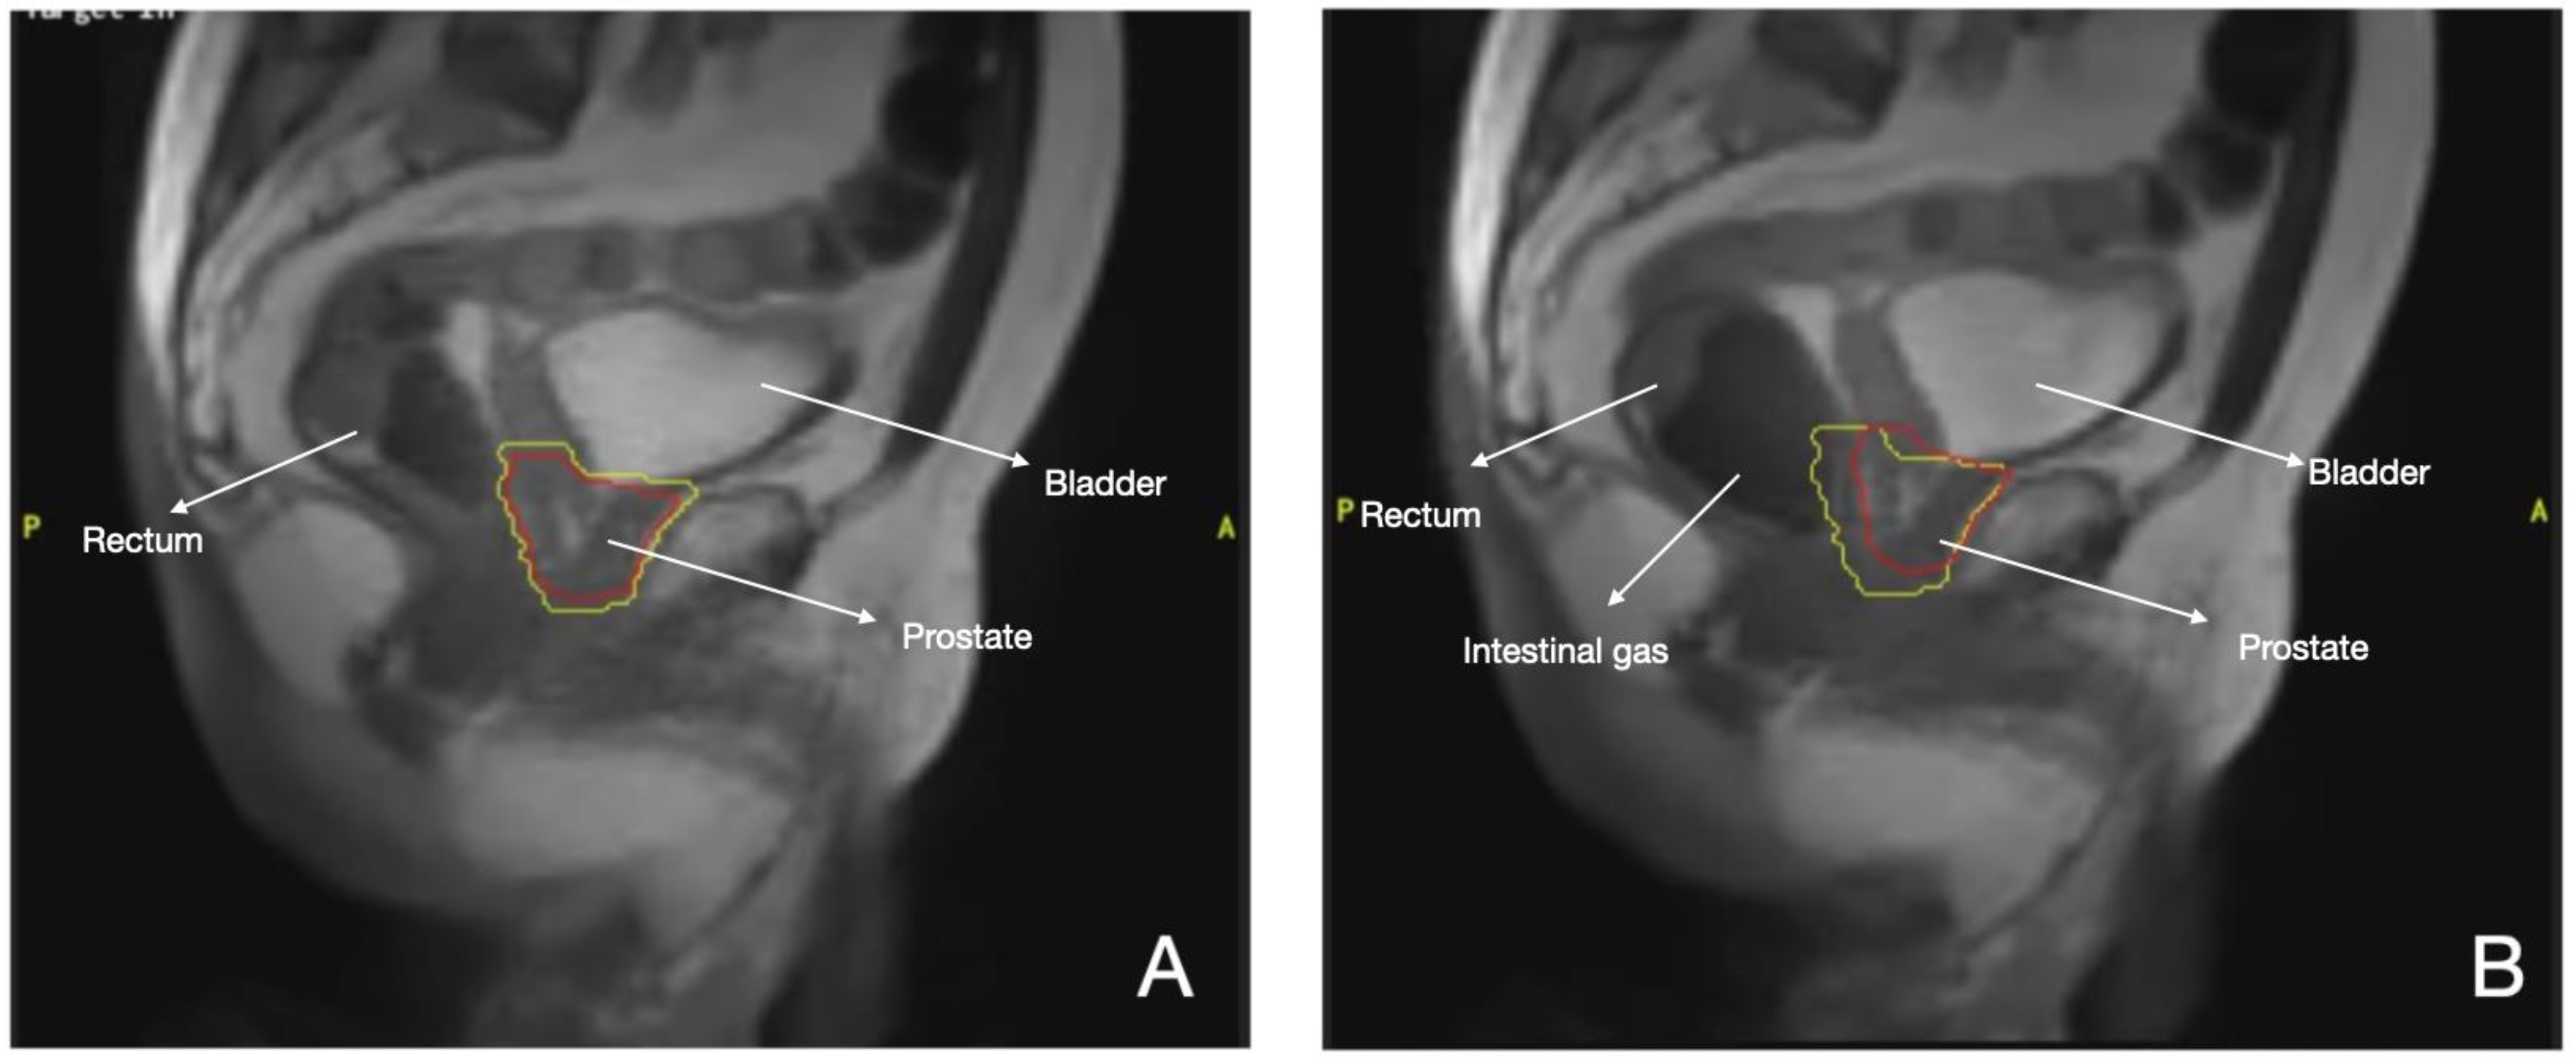

3.1. Prostate Cancer

- Chiloiro, G.; Boldrini, L.; Meldolesi, E.; Re, A.; Cellini, F.; Cusumano, D.; Corvari, B.; Mantini, G.; Balducci, M.; Valentini, V.; et al. MR-guided radiotherapy in rectal cancer: First clinical experience of an innovative technology. Clin. Transl. Radiat. Oncol. 2019, 18, 80–86. [Google Scholar] [CrossRef] [PubMed]

- Intven, M.; Otterloo, S.d.M.v.; Mook, S.; Doornaert, P.; Breugel, E.d.G.-V.; Sikkes, G.; Willemsen-Bosman, M.; van Zijp, H.; Tijssen, R. Online adaptive MR-guided radiotherapy for rectal cancer; feasibility of the workflow on a 1.5T MR-linac: Clinical implementation and initial experience. Radiother. Oncol. 2020, 154, 172–178. [Google Scholar] [CrossRef]

- Eijkelenkamp, H.; Boekhoff, M.R.; Verweij, M.E.; Peters, F.P.; Meijer, G.J.; Intven, M.P. Planning target volume margin assessment for online adaptive MR-guided dose-escalation in rectal cancer on a 1.5 T MR-Linac. Radiother. Oncol. 2021, 162, 150–155. [Google Scholar] [CrossRef]